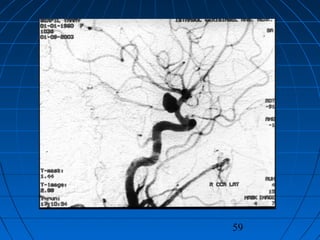

MOYA - MOYA HASTALIĞIMOYA - MOYA HASTALIĞI

 İntrakranyal arter sistemininİntrakranyal arter sisteminin

anormal gelişimi ileanormal gelişimi ile ince ağsıince ağsı

damardamarlar oluşumular oluşumu

 ÇokluklaÇoklukla karotis sistemindekarotis sisteminde

 Çocuklar ve genç erişkinlerdeÇocuklar ve genç erişkinlerde

sıksık

 İskemi veya kanamaİskemi veya kanama

 Tanı yolları aynıTanı yolları aynı

 Özel cerrahi girişimlerle tedaviÖzel cerrahi girişimlerle tedavi